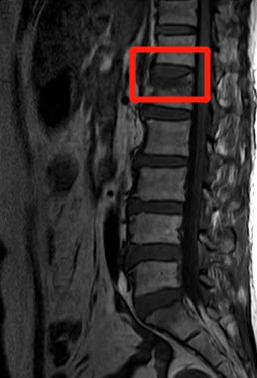

经过谢文伟主任认真细致的检查,王阿姨被诊断为“老年性骨质疏松伴腰1椎体压缩性骨折”。

王阿姨腰椎磁共振图像

王阿姨入院后,谢主任为王阿姨进行了微创手术---腰椎椎体成形术。术后当天,王阿姨的腰痛就明显缓解,第二天就能下床正常活动了。